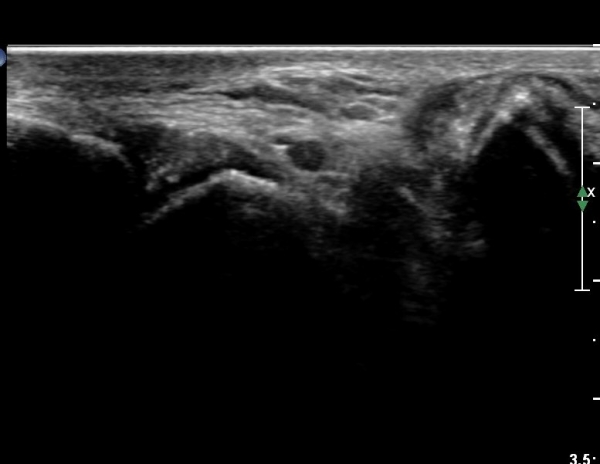

Á¾°ñ Àü¹æ µ¹±â(anterior process) °ñ±Ø°ú Ȱ¾×¸·¿° ¼Ò°ßÀ» º¸ÀÓ(»çÁø 3, 4).

Sinus tarsi Á¾´Ü¸é, Ⱦ´Ü¸é°Ë»ç¿¡¼­ sinus tarsi ³» ºÎÁ¾À» º¸ÀÓ(»çÁø 5, 6).